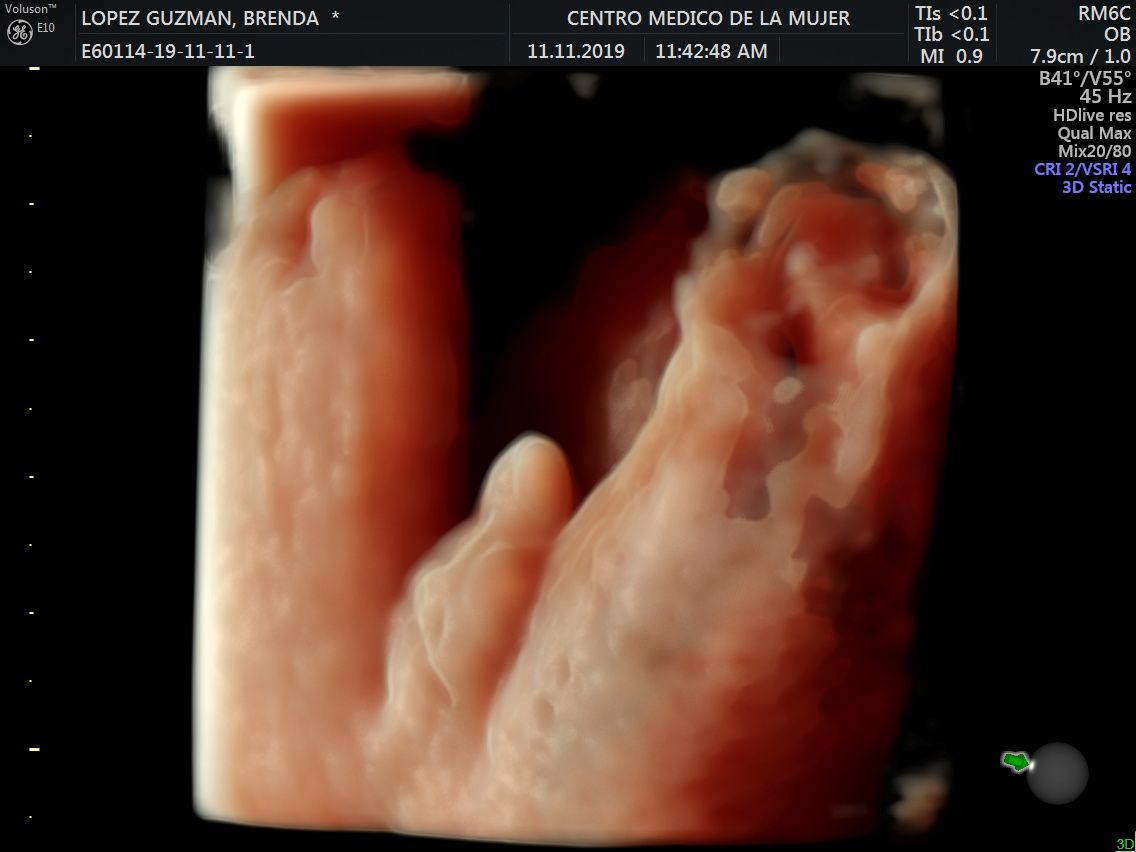

Fotos y videos

ECO Anatómico

Consiste en la evaluación especifica de cada organo y sistema del bebé con medidas detalladas de cada parte para evaluar su crecimiento proporcional.